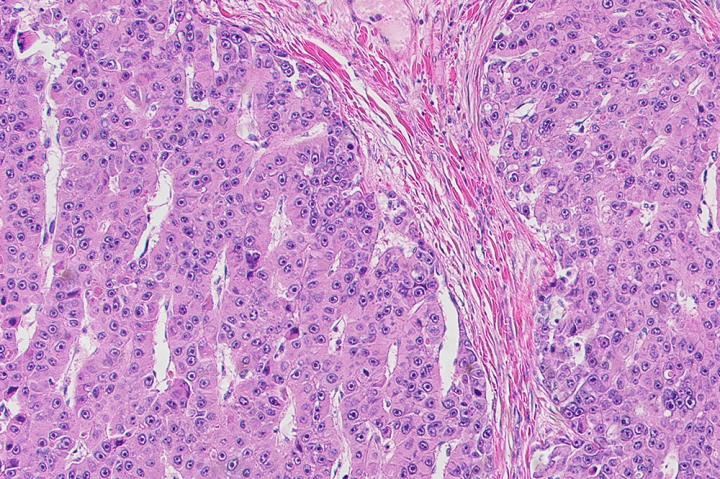

image: New drugs to eliminate fibrolamellar tumors cells, pictured here, were identified using an expedited approach. view more

Credit: Laboratory of Cellular Biophysics at The Rockefeller University